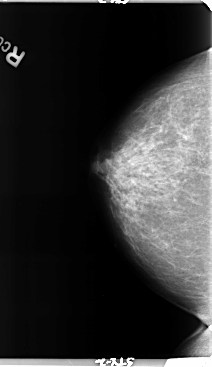

B_3158_1.RIGHT_MLO

RIGHT_CC LINES 4760 PIXELS_PER_LINE 2744 BITS_PER_PIXEL 12 RESOLUTION 50 NON_OVERLAY

RIGHT_MLO LINES 4776 PIXELS_PER_LINE 3008 BITS_PER_PIXEL 12 RESOLUTION 50 NON_OVERLAY